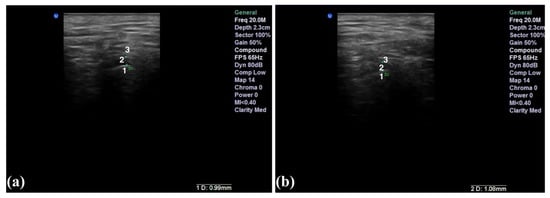

2.3. The Ultrasound Examination

- Talmaceanu, D.; Lenghel, L.M.; Bolog, N.; Stanila, R.P.; Buduru, S.; Leucuta, D.C.; Rotar, H.; Baciut, M.; Baciut, G. High-resolution ultrasonography in assessing temporomandibular joint disc position. Med. Ultrason. 2018, 20, 64–70. [Google Scholar] [CrossRef] [Green Version]

- Talmaceanu, D.; Lenghel, L.M.; Bolog, N.; Buduru, S.; Leucuta, D.; Horatiu, R. High-resolution ultrasound imaging compared to magnetic resonance imaging for temporomandibular joint disorders: An in vivo study. Eur. J. Radiol. 2020, 132, 109921. [Google Scholar] [CrossRef]

- Elias, M.F.; Birman, E.G.; Matsuda, C.K.; Oliveira, I.R.S.; Jorge, W.A. Ultrasonographic findings in normal temporomandibular joints. Braz. Oral. Res. 2006, 20, 25–32. [Google Scholar] [CrossRef]